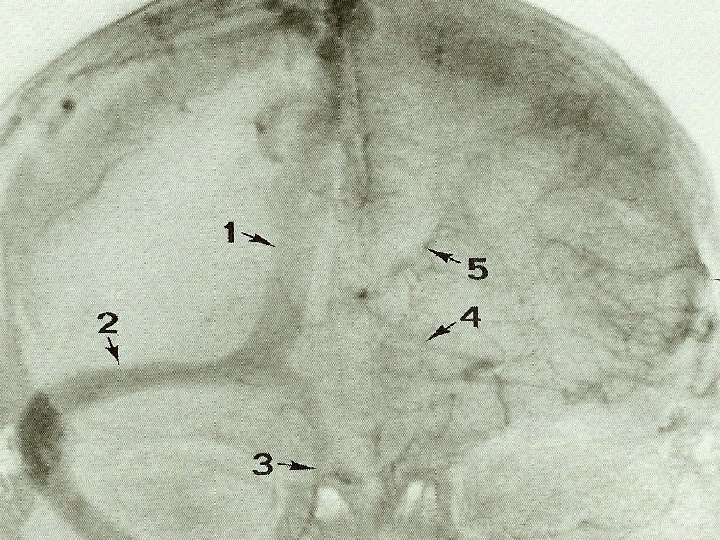

Scout view Michigan Neurosurgery